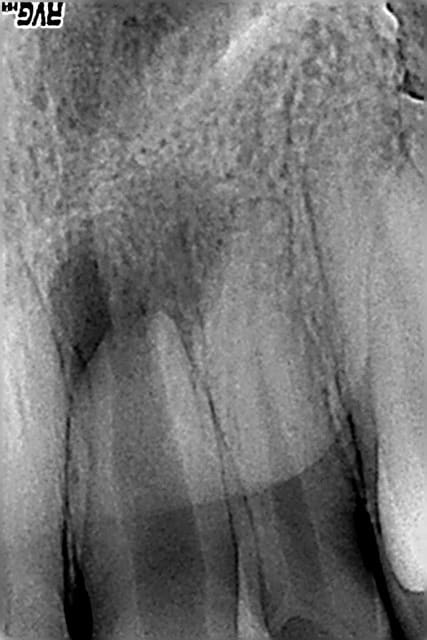

photos jointes: cas de resorption externe avec à l'origine faux canal, félure ou juste la resorption qui avait atteint le canal...

Obturée à la biodentine allongée, pose de srew post titane dans la foulée de l'obturation, un moignon compo a été réalisé ensuite.

Dent traitée en urgence (abcès), ça saignait mais j'ai pu cauteriser (merci lokki), une galère si j'avais voulu mettre de la gutta.... perdue pour perdue j'ai tenté le truc, c'était en janvier 2014 et la dent, recoiffée depuis est toujours là, asymptomatique.

La patiente est prevenue que ça tiendra ce que ça tiendra et qu'elle doit faire des economies pour eventuel implant à venir (ou vacances avec son copain si l'implant tarde à venir).